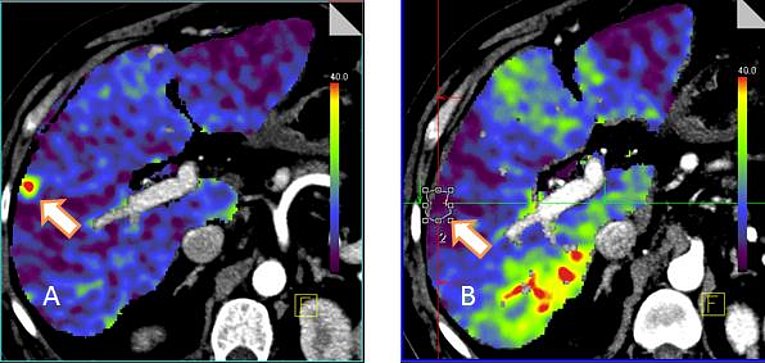

Hierbei werden Lebertumore über eine CT-gesteuerte Punktion in lokaler Betäubung oder gelegentlich in Vollnarkose über eine Nadel verkocht. Das Verfahren ist relativ schonend und meist nur mit einem 2-tägigen Krankenhausaufenthalt verbunden.